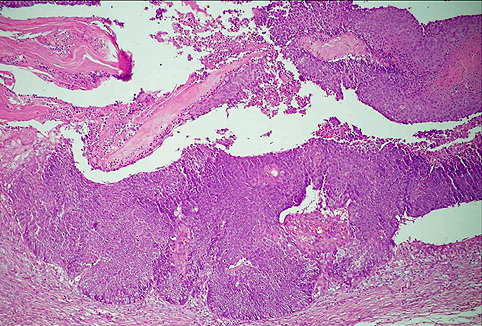

Pilomatricoma--perforating pilomatricoma = ورم أم الشعرة الثاقب